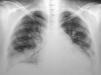

Los exámenes de laboratorio al ingreso mostraron glucosa, creatinina, ionograma y enzimas musculares dentro de límites normales. En el hemograma se evidenciaron hematocrito del 27%, hemoglobina de 7,9g/dl, recuento de glóbulos blancos de 4.600/ml, con fórmula leucocitaria y plaquetas normales. La velocidad de sedimentación globular y la proteína C reactiva fueron de 89mm/h y 6,3mg/dl, respectivamente. El sedimento de orina mostró proteínas (++) y glóbulos rojos (++). El urocultivo y el hemocultivo seriado fueron negativos. La Rx simple de tórax puso en evidencia silueta cardíaca aumentada de tamaño, compatible con derrame pericárdico, discreta procidencia del arco mediomediastinal izquierdo, refuerzo de la trama pulmonar bibasal y senos costofrénicos libres. Electrocardiograma con frecuencia cardíaca de 110/min, PR de 160ms, QRS de 80ms, aQRS de 0°, ondas T negativas en D III, V1-V2 con extrasístoles ventriculares aisladas. La ecocardiografia Doppler mostró el ventrículo izquierdo de dimensiones normales, motilidad y engrosamiento sistólico parietal, sin alteraciones segmentarias. La fracción sistólica del ventrículo izquierdo estaba conservada. La aurícula izquierda, las cavidades derechas y las válvulas aórtica, pulmonar y tricúspide fueron normales. Se observó derrame pericárdico moderado a severo con colapso parcial de la aurícula derecha sin variabilidad respiratoria del flujo transmitral mayor al 10%. La aorta mostró raíz de diámetro normal. Fue difícil estimar la PSAP. La fracción de eyección era del 66%. Durante el día 7 de la internación se repitió la ecocardiografía Doppler constatándose progresión del derrame pericárdico con PSAP de 43mm, por lo que se derivó a unidad de tratamientos intensivos. Permaneció con registros febriles diarios mayores a 38°C y estertores crepitantes pulmonares bibasales. Se repitieron hemocultivos seriados y urocultivos que resultaron negativos. En el examen analítico presentó hematocrito del 21%, hemoglobina de 6mg/dl, ferremia de 16mg/dl, recuento de glóbulos blancos de 2.800/ml con fórmula normal. Glucemia, uremia y creatininemia con valores normales. Una prueba de Coombs resultó (+). Se interpretó el cuadro actual como exacerbación de su enfermedad de base y se realizaron pulsos de betametil prednisolona de 1g/día por 3 días consecutivos. Se realizó, además, una hemotransfusión con concentrado de glóbulos rojos. En los días subsiguientes evolucionó afebril, sin signos de insuficiencia cardíaca. Se indicó hierro y leucovorina. El día 10 de internación la paciente presentó disnea de reposo. La Rx simple de tórax evidenció aumento progresivo de la silueta cardíaca, ensanchamiento mediastinal vascular, desaparición de los ángulos costofrénicos y radioopacidades reticulonodulillares perihiliares bilaterales y bibasales, con predominio derecho (fig. 1). La TC de tórax de alta resolución mostró leve cardiomegalia, derrame pericárdico, derrame pleural bilateral de leve volumen con predominio derecho; áreas de vidrio esmerilado en parches, segmentarias, bilaterales, predominando en campos pulmonares inferiores; áreas de atrapamiento aéreo, subpleurales, bilaterales con predominio de campos pulmonares superiores; opacidades reticulonodulillares bibasales, y líquido en cisura menor (fig. 2).